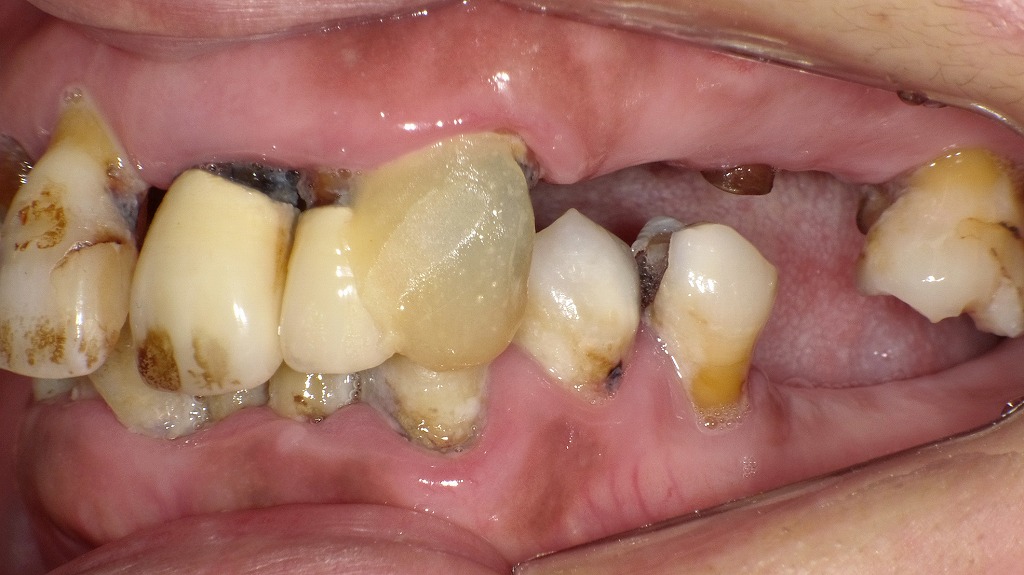

この画像では、歯面に大量の歯垢・歯石が付着し、複数歯に進行した虫歯が認められます。歯周病や虫歯の原因となる細菌は、炎症で傷ついた歯肉から血管内に入り込み、動脈硬化を進行させるリスクがあることがわかっています。口腔内の細菌は局所にとどまらず、血液を介して全身に影響を及ぼす可能性があるため、適切なプラークコントロールと早期治療が全身の健康維持にも重要です。